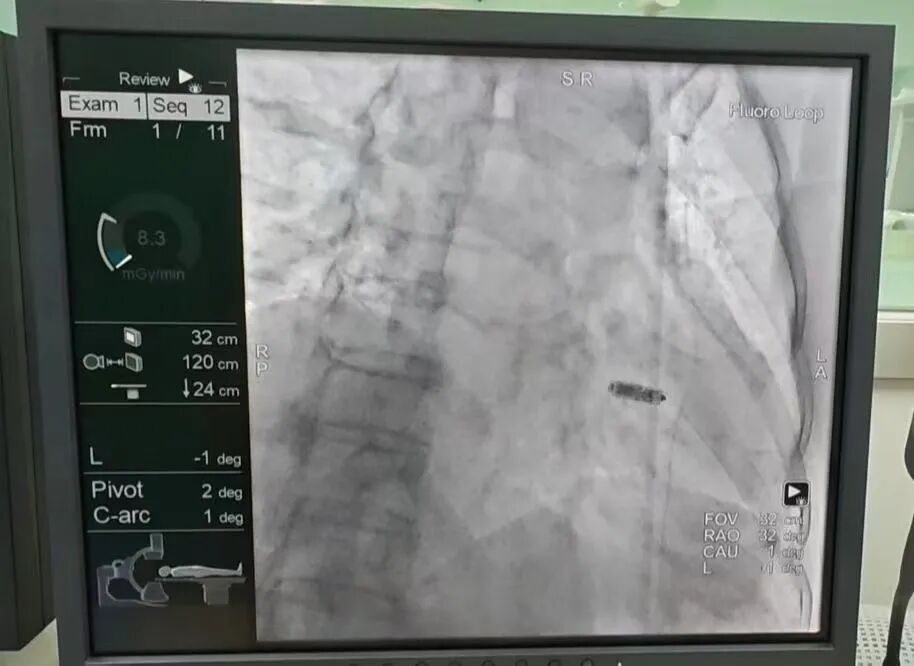

6、新疆医院首例食管胃吻合口狭窄球囊扩张术圆满成功

12月15日,消化科驻疆专家万晓龙主任领衔团队,成功为食管癌术后吻合口狭窄患者实施内镜下球囊扩张术(EBP)。这是新疆医院首例消化道狭窄微创介入手术,不仅为患者重建了进食通路,标志着新疆医院在消化内镜微创治疗领域实现"零的突破"。